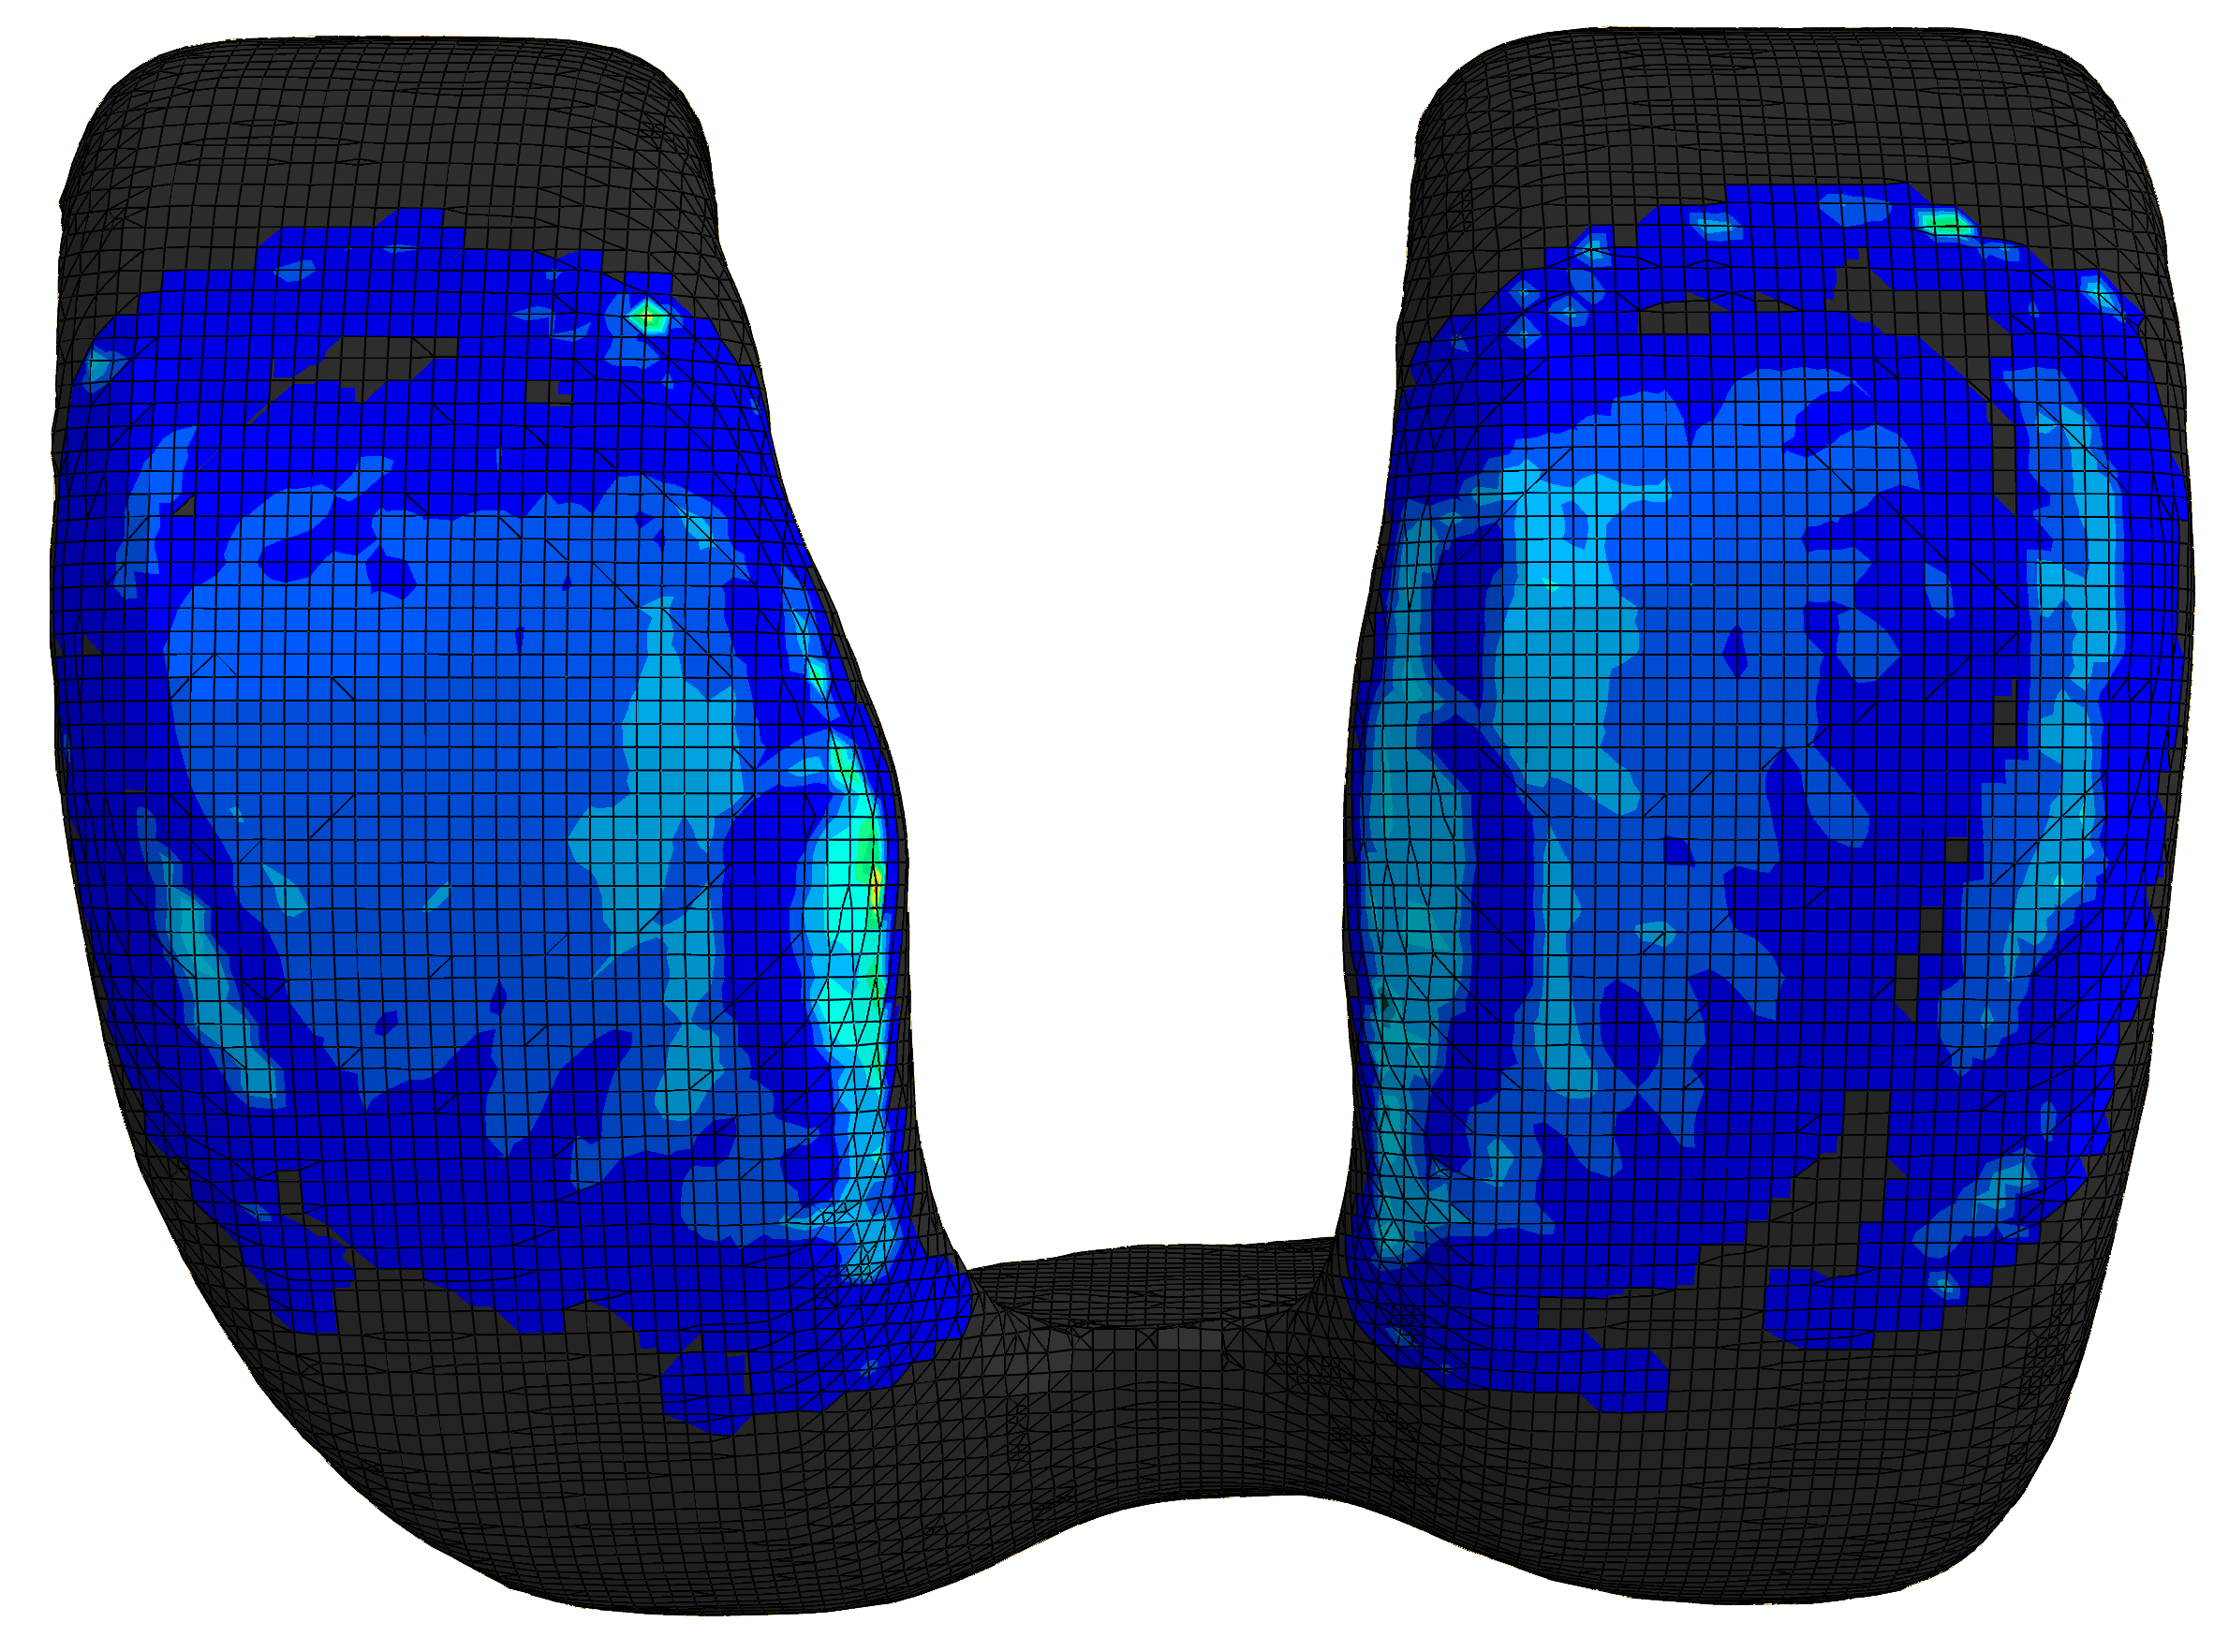

The bottom surface of the tibia head is fixed, and two translational DOFs in the horizontal plane of the top surface of the femur head are also constrained. On the top surface of the femur head, a vertical load of up to [72] is applied to induce contact in the knee joint. The displacement contours () from different views are shown in Fig. 32. It is obvious that the deformation occurs mainly in the meniscus. The femur, tibia and articular cartilages are similar to rigid bodies. This phenomenon meets the expectation because the Young’s modulus of the meniscus is significantly smaller than those of the bones and articular cartilages. The meniscus is squeezed into the joint space and there is lateral extension of the meniscus. The large deformation of the meniscus increases the contact area which is helpful to reduce the contact pressure.

The contact pressure distributions () are depicted in Fig. 33. To illustrate the distribution clearly, contact pressure values smaller than are not included in the contour. It is obvious that the contact pressure on the articular cartilage has a similar distribution and magnitude compared to that on the meniscus. Besides, the contact pressure on the articular cartilage has a similar distribution from Ref. [72].

The development of the contact on the articular cartilage is recorded, as depicted in Fig. 34. Note that only the area where the contact pressure is greater than has been taken into account. Generally speaking, with increasing the vertical load , the contact area is increasing while its increasing rate is reducing. The average contact pressure increases during the loading history. Before the vertical load increases up to , the increasing rate of the average contact pressure is basically reducing. However, when the average contact pressure increases almost linearly because the contact area increases only slightly.